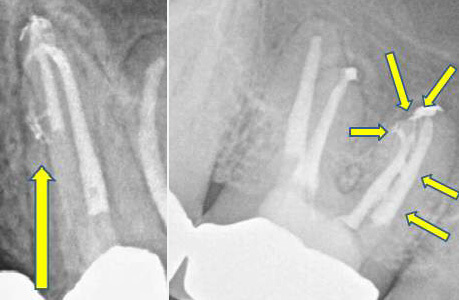

In manchen Fällen hat man bei der Wurzelkanalrevision mit besonders schwierigen Umständen zu kämpfen. Dieses z. B. aufgrund von Materialermüdung abgebrochener Wurzelkanalinstrumente. Die Entfernung dieser Instrumente ist oftmals möglich, gleichzeitig jedoch sehr zeitaufwändig. In jedem Fall wird die individuelle Situation Ihres Zahnes vor jeder Behandlung von uns analysiert und mit Ihnen besprochen. Eine ehrliche Einschätzung zur Prognose Ihres Zahnes wird Ihnen die Entscheidung zum Erhalt oder Nichterhalt leicht machen.

Bild links: Oberer Backenzahn mit abgebrochenem Instrument in der vorderen-äußeren Wurzel.

Bild rechts: Nach Entfernung des Instrumentenfragmentes ist die Instrumentierung und Reinigung des Wurzelkanals möglich (Röntgenkontrastaufnahme).